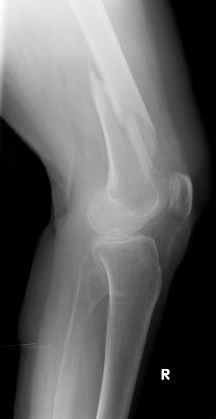

Уважаемые коллеги, Было бы интересно узнать вашу тактику при остеосинтезе этого перелома.

С уважением Вальдемар.